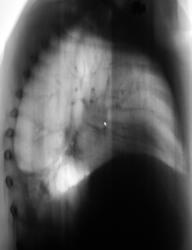

Пациент был направлен в рентгеновский кабинет терапевтом с диагнозом "Правостороняя пневмония". Было произведено стандартное исследование.

Было назначено противовоспалительное лечение. Через 1 неделю проведен "рентген-контроль".

Еще через неделю, также произведен "рентген-контроль".

Сегодня произвели "очередной контроль". Произвели рентгенографию в прямой и правой боковой проекциях. Решили также произвести томографию в правой боковой проекции.

правостороннего плеврального выпота в проекции средней доли.

Согласен с коллегой, но по-моему, кроме это выпот есть и заднем синусе. Картина в серия снимков №7-9, с небольшой положительной динамикой в сравнении данными в серии №4-6.

Кажущееся затемнение в области средней доли симулирует суперпозиция приподнятого правого купола диафрагмы и тени сердца. В заднем синусе справа - небольшой выпот, а со стороны диафрагмы, кроме элевации и выпрямления, присутствует картина диафрагматита в задних отделах. Вероятно необходимо ультразвуковое исследование органов брюшной полости и забрюшинного пространства для поиска первопричины данного состояния там. Динамика процесса за время наблюдения - явно положительная.